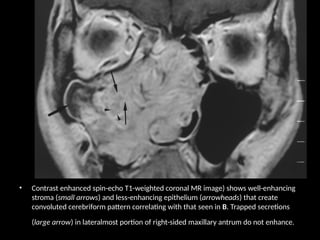

• Unenhanced fast spin-echo T2-weighted coronal MR image reveals convoluted cerebriform

pattern throughout mass. Pattern consists of low-signal-intensity (arrowheads) and relatively

high-signal-intensity (small arrows) striations that probably represent metaplastic squamous

epithelium and edematous stroma, respectively. Secretions after obstruction in lateralmost

portion of right-sided maxillary antrum are of extremely high signal intensity (large arrow).

• Contrast enhanced spin-echo T1-weighted coronal MR image) shows well-enhancing

stroma (small arrows) and less-enhancing epithelium (arrowheads) that create

convoluted cerebriform pattern correlating with that seen in B. Trapped secretions

(large arrow) in lateralmost portion of right-sided maxillary antrum do not enhance.

• Unenhanced fastspin-echo T2-weighted coronal MR image reveals convoluted cerebriform pattern throughout mass. Pattern consists of low-signal-intensity (arrowheads) and relatively high-signal-intensity (small arrows) striations that probably represent metaplastic squamous epithelium and edematous stroma, respectively. Secretions after obstruction in lateralmost portion of right-sided maxillary antrum are of extremely high signal intensity (large arrow).

• 27.

• Contrast enhancedspin-echo T1-weighted coronal MR image) shows well-enhancing stroma (small arrows) and less-enhancing epithelium (arrowheads) that create convoluted cerebriform pattern correlating with that seen in B. Trapped secretions (large arrow) in lateralmost portion of right-sided maxillary antrum do not enhance.